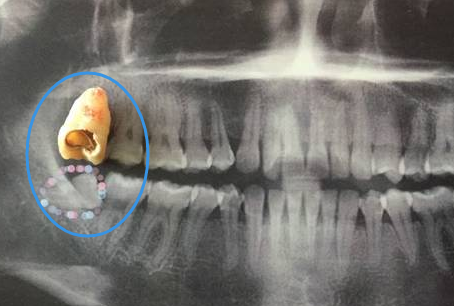

深圳牙科醫院醫生表示,因為(wei) 智齒拔牙難度比較大,創傷(shang) 也較大,恢複起來會(hui) 稍微慢一點,所以在麻醉藥物失效後就會(hui) 有疼痛和腫脹等症狀出現,這是正常的,大家不需要擔心。醫生會(hui) 根據拔牙難度開具一些止痛藥和消炎藥。

至於(yu) **要不要吃止痛藥,大家就需要聽從(cong) 醫生醫囑,如果能夠忍受,可以不吃,如果疼痛嚴(yan) 重,無法忍受,不要強忍,需要及時吃止痛藥和消炎藥進行緩解,而且在拔牙後還可以24小時內(nei) 冰敷緩解疼痛腫脹的情況。